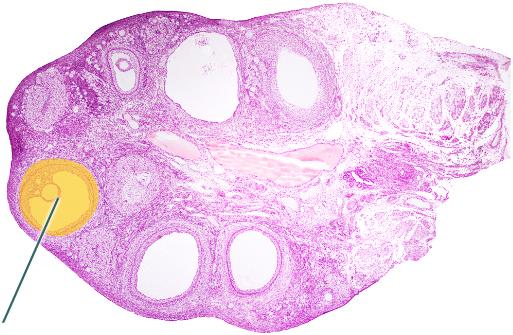

Identify the highlighted layer of the uterine wall

Endometrium

Identify the highlighted cells

Interstitial Cells

Identify the highlighted uterine layer.

Myometrium

Which hormone stimulates contraction of the highlighted layer? (Myometrium)

Oxytocin

Identify the highlighted structure.

Oocyte

Identify the highlighted structure.

Mature Tertiary Follicle